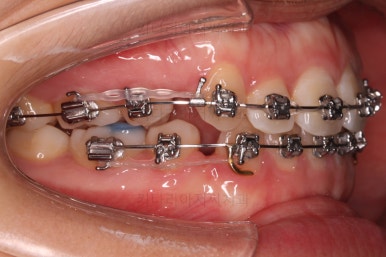

사용한 장치 : 자가결찰 금속(엠파워 메탈, Empower metal) + 미니스크류

초진 시 입안의 모습이에요. 치열이 많이 나쁜 편은 아니고 앞니쪽이 조금 삐뚤어져 있네요.

특히 윗니 작은 앞니 하나가 아랫니보다 안으로 쑥 들어가 있어서 옆에 있는 송곳니가 덧니처럼 보여요.

이번 환자분이 선택하신 장치는 엠파워 메탈이라고 하는 자가결찰 금속장치에요.

철사를 잡아주는(결찰) 뚜껑이 장치에 달려있는 (자가)장치이며, 재질이 금속인 장치에요.

금속 장치는 가장 튼튼하고 부피도 작고 비용도 저렴하다는 장점이 많은 장치입니다.

장치 부착 직후의 느낌을 참고해 주세요.

적절한 시기에 발치를 하고요.

앞니의 덧니 느낌은 벌써 많이 좋아졌네요.